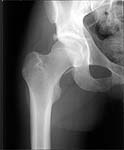

22 yrs man , semiprofessional( he earn some money from playing) basketball player got suffered in car accident.He had hip joint posterior luxation ( Pipkin 4) with little acetabular roof fragments ( nondisplaced) and anterosuperior abruption fracture of the head of the femur.

Additional injuries were severe face wounds. Emergency manipulations were reposition of the hip luxation under the radiologic control and wounds care. After reposition the CT scan was made. We found 2x3cm wide and 0.5 thick OCH fragment outside the joint surfaces , under the caput. The traction was applied.

Here are the missing postreduction views.